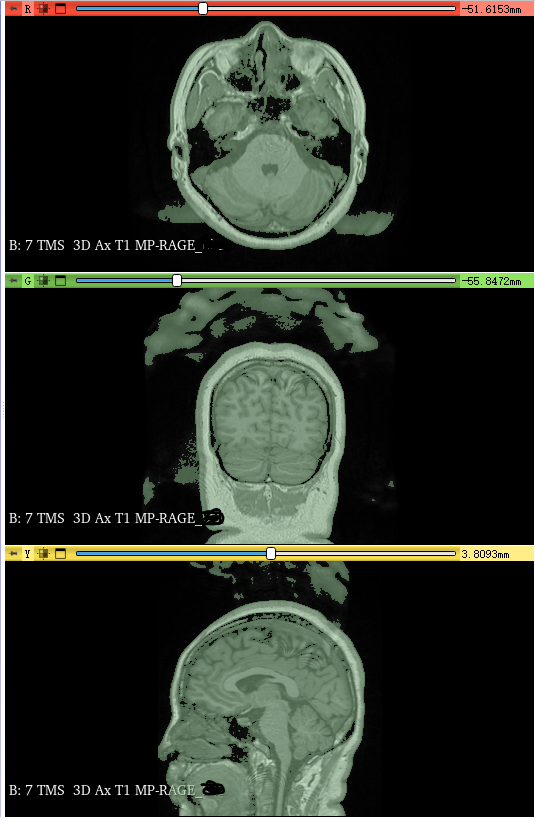

(4)查看输出

可以看出我的输出影像很干净了,没有头顶杂块,3D 模型也很干净,意味着我的杂块已经顺利去除了。